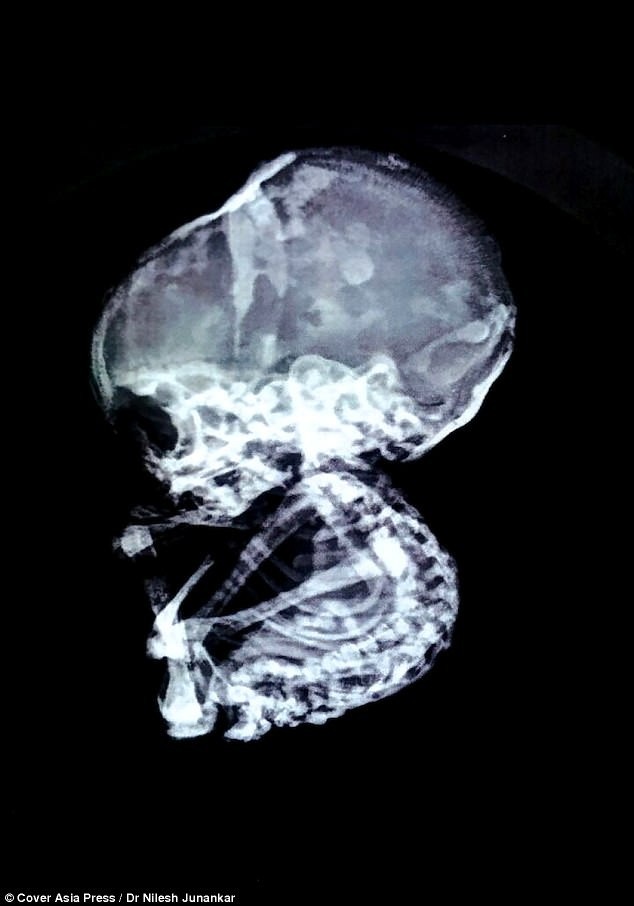

BS. Nilesh Junankar, người thực hiện ca phẫu thuật, cho biết chụp CAT cho thấy có một khối gây tắc nghẽn ruột và có cấu trúc như một khối đá.

Bào thai khi lấy ra có cấu trúc xương khá hoàn chỉnh

Tiếp tục thực hiện nội soi, các bác sĩ của TT phẫu thuật Junankar (Nagpur) đã vô cùng sốc khi phát hiện khối đá gây tắc ruột đó là một thai nhi 4 tháng tuổi.

Bào thai đá vô cùng hiếm gặp với chỉ 300 ca được ghi nhận trên toàn thế giới trong 400 năm qua.